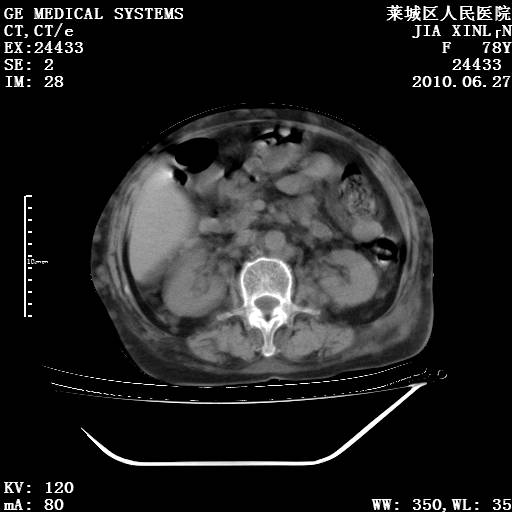

以下是引用胡宇在2010-7-2 19:11:00的发言:[br]神经纤维瘤的特点为:肿块呈多发性、数目不定,少的几个,多的可成百上千难以计数。小的如米粒,大的似拳头,甚至可达十数公斤以上。可松弛地悬挂于皮表,皱褶及松弛可致畸形明显。神经纤维瘤沿神经干的走向生长时呈念珠状,或蚯蚓块状形结节。此外神经纤维瘤皮肤可出现咖啡斑,大小不一,形如雀斑小点状,或大片状,分布与神经纤维瘤肿块的分布无关。肿瘤数目不多的患者,皮肤色素咖啡斑状沉着是纤维神经瘤的重要诊断之一。 本病多发于躯干,有时出现于四肢及面部,患者常合并许多疾病应予重视加以区别。 [br] [br] [br] [br]lyb999说 [br]